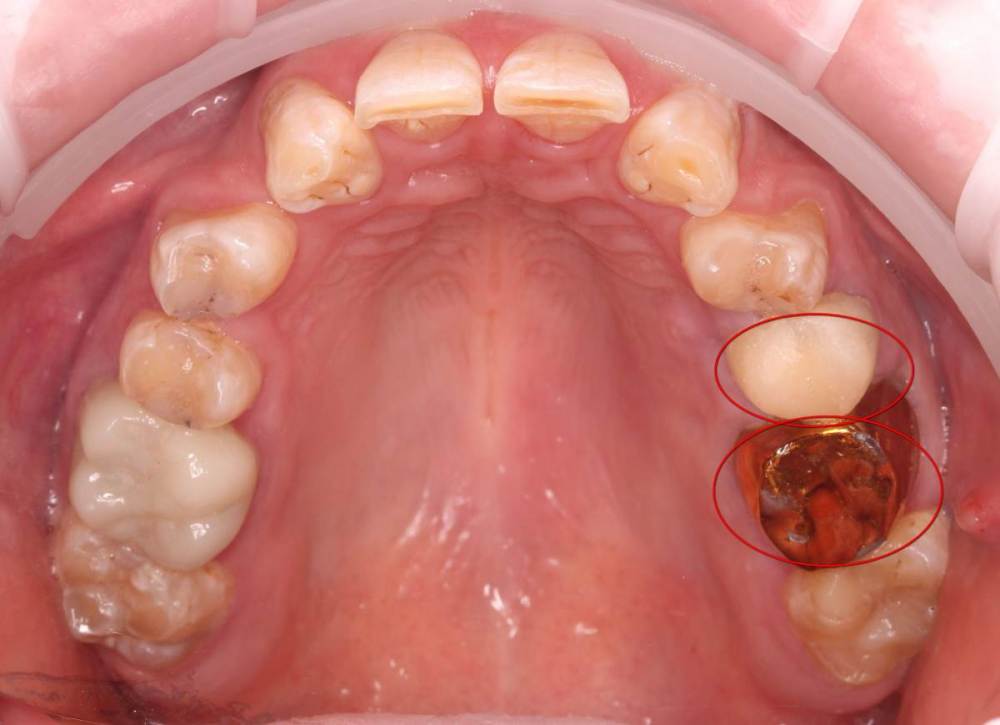

Роман1982 Опубликовано 25 мая, 2021 Поделиться Опубликовано 25 мая, 2021 Добрый день! Очень хотелось бы услышать объективное мнение специалистов. 40 лет На верхней челюсти от рождения не хватает двух резцов (12 и22) Перекрестный прикус В принципе, особо не беспокоит, хотя есть щелчки в суставе слева, если широко открывать челюсть. Из-за неправильно проводимого ранее лечения, встал вопрос об удалении в ближайшее время 25 и 26 зуба сверху и 46 снизу (на фото обведены красным). Ортопед рекомендовал пройти ортодонтическое лечение, т.к. в противном случае в дальнейшем могут возникнуть сложности с имплантами и коронками, может ухудшиться ситуация с суставом. Вот пытаюсь взвесить все за и против. Понимаю, что прикус было бы желательно исправить. Но! При текущем состоянии зубов не навредит ли это им еще больше? Исправление прикуса повлечет за собой необходимость установки на верхней челюсти еще двух дополнительных имплантов (на месте отсутствующих12 и 22). После исправления прикуса велика вероятность тотального протезирования. По словам того же ортопеда, может не хватить высоты сустава и тогда на все зубы понадобиться устанавливать коронки. Стоит ли затевать ортодонтическое лечение в данной ситуации или лучше не трогать то, что как-то функционировало 40 лет? Хотелось бы услышать аргументирование мнение. Ссылка на комментарий